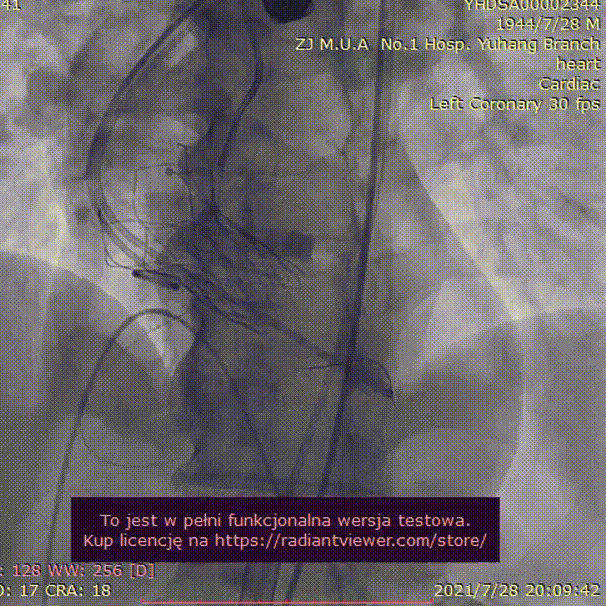

手术过程:

23mm球囊预扩

(有腰征,无返流)

开始释放后再次定位

23mm球囊后扩

植入后造影

术后压差1mmHg

术中经食道心超评估:

人工主动脉瓣:植入深度 7mm,峰值流速1.2m/s,峰值压差6mmHg,平均跨瓣压差3mmHg,原左-右冠窦结合部微量瓣周漏。